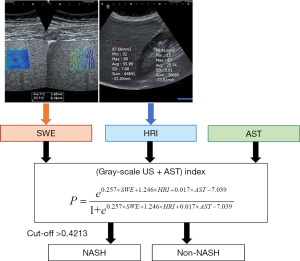

The results of univariable logistic regression analysis of laboratory data are shown in Table 4. AST [odds ratio (OR), 1.021; P=0.015], ALP (OR, 1.019; P=0.037), and TG (OR, 0.988; P=0.030) were the significant factors associated with NASH. These factors were entered into the multivariable logistic regression analysis, revealing that AST was the only independent factor for predicting NASH (OR, 1.019; P=0.032) (Table 4). Therefore, various US indices were developed by combining US parameters with or without AST. Table 5 shows the diagnostic performance of various US indices. Among the US indices, the index consisting of gray-scale US parameters (SWE and HRI) and AST demonstrated the best diagnostic performance. The index was obtained as follows based on the multivariable logistic regression model using SWE, HRI, and AST (Figure 3).

This can be expressed in the form of predicted probability with a value between 0 and 1.

ROC curve analysis of this index revealed an AUC of 0.806 with an optimal cutoff value of 0.4213. The corresponding sensitivity and specificity were 68.0 and 80.0%, respectively (Table 5, Figure 4). The US index consisting of gray-scale US parameters and AST showed higher AUC than other indices with a significant difference compared to the Fibroscan index (AUC, 0.806 vs. 0.687, P=0.04) and no statistically significant difference from other indices.